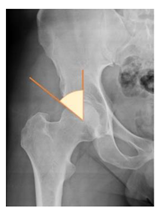

Preoperative and postoperative radiographic data are reported in Table 4. Preoperatively, 18 THR (24.3%) were implanted in skeletally immature children with closed triradiate cartilage (1 ≤ Risser ≤ 3). Radiographic acetabular insufficiency (LCEA < 25° and AI > 13°) was detected in 14 hips (18.9%), while protrusion was present in 3 hips (4.1%) An excessive valgus of the femoral neck was observed in 19 hips (25.7%), while an important varus deformity was present in 7 hips (9.5%).

In our experience, implant malposition was the only reason for implant revision. In one case, progressive subsidence was observed in a varus undersized stem, implanted in a boy with Albers–Schömberg disease; in another case, an excessively vertical cup with a 28 mm femoral head caused hip instability and required cup revision.

THR can be a challenging procedure in very young people. The combination of distorted anatomy, small physique, and poor bone stock can impede proper implant placement. Implant sizing may be an issue in these patients. The combination of young age and peculiar conditions such as skeletal dysplasia may require particular attention in preoperative planning and implant selection. Noticeably, we used the smallest size of the cup in 11 hips (15%) and the smallest size of the stem in 14 hips (19%). A meticulous preoperative planning, even using simulation software, [40,41,42] and careful implant selection, sometimes requiring even customized implants [37], is crucial in such conditions, to prevent unpleasant pitfalls during the operation.